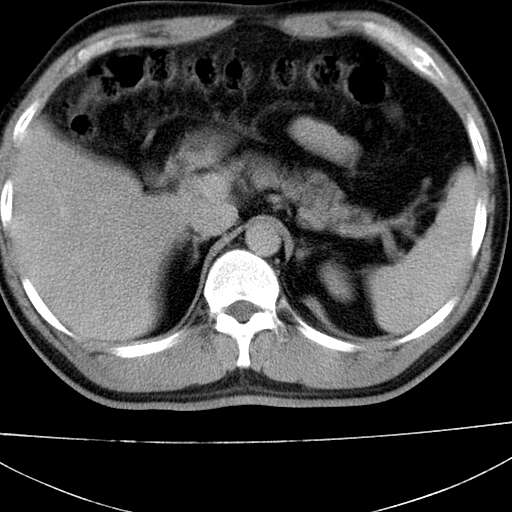

标题: CT21921:腹膜后腔肿物。患者男39Y。体检。增强扫描时间欠准 [打印本页]

标题: CT21921:腹膜后腔肿物。患者男39Y。体检。增强扫描时间欠准

左侧膈肌脚外缘见一结节样软组织影,密度较均匀,与胸膜关系稍密切,增强轻度强化;考虑来自胸膜良性病变(胸膜纤维瘤可能)。建议加扫胸部ct检查。

2、左下膈肌脚外缘结节状病变,与胸膜交界面呈锐角,胸膜下脂肪线可见,定位于肺内,考虑支气管囊肿或肺隔离征可能性大。

1)考虑左肺下叶后基底段(或左下胸后壁胸膜)软组织团块,性质待定;建议行进一步检查。2)左肾结石。

左膈肌连续性中断,左侧膈疝可能性大.

左膈肌角后腹膜腔见肿物影,其内见脂肪密度灶及软组织密度灶,强化不明显。病灶大部在后腹膜内。考虑异位嗜铬细胞瘤或脂肪肉瘤、畸胎瘤

考虑左肺下叶后基底段肺隔离症?胸膜间皮瘤?

左下肺隔离症,可见从胸主动脉发出异常血管供应